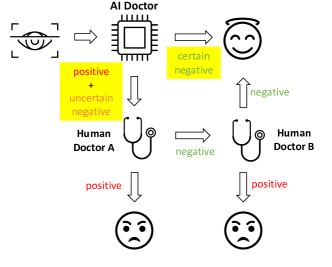

When using AI for diagnostic applications, false negative decisions are often concerning and costly. If a disease case is mistaken for an healthy condition, the patient may miss the best time for treatment and may suffer from more severe consequences. We consider an uncertainty-informed human-AI collaborative scheme, where a set of “uncertain negative” decisions are first identified based on the negative decisions made by an ensemble model, and then human diagnosticians are involved to re-examine these uncertain cases to identify false negatives. We formulate our research problem under the above scheme, and aim to design approaches to maximize the number of corrected wrong predictions. The contributions of this paper are three:

We consider an uncertainty-informed diagnostic scheme as an application of prediction uncertainties that fosters the collaboration between human and AI diagnosticians, illustrated in Figure 1. In this scheme, an AI model is first used to screen the images. The cases diagnosed as positive will be referred to a human diagnostician, who will confirm the case as positive if she agrees with the AI (that the image corresponds to a positive case). If the AI and the human diagnostician disagree, another human diagnostician will be involved to make the final decision (as an arbitrator between AI and the first human diagnostician). For comparison, we will consider a baseline scheme where only the positive cases will be sent to human diagnosticians. The baseline scheme suffers from the problem that false negatives from the AI’s diagnoses would never be reviewed by human diagnosticians.